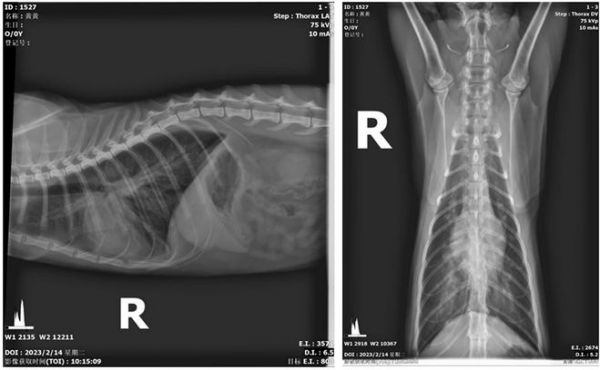

图1 胸部DR

7.3 影像学检查

X线胸腔侧位片可以看到肺前叶动静脉有增粗表现,同时肺后叶有液体渗出表现,腹部超声可以明显看到肝静脉有扩张表现,双肾形态未见明显异常,同时下泌尿道未见梗阻迹象。